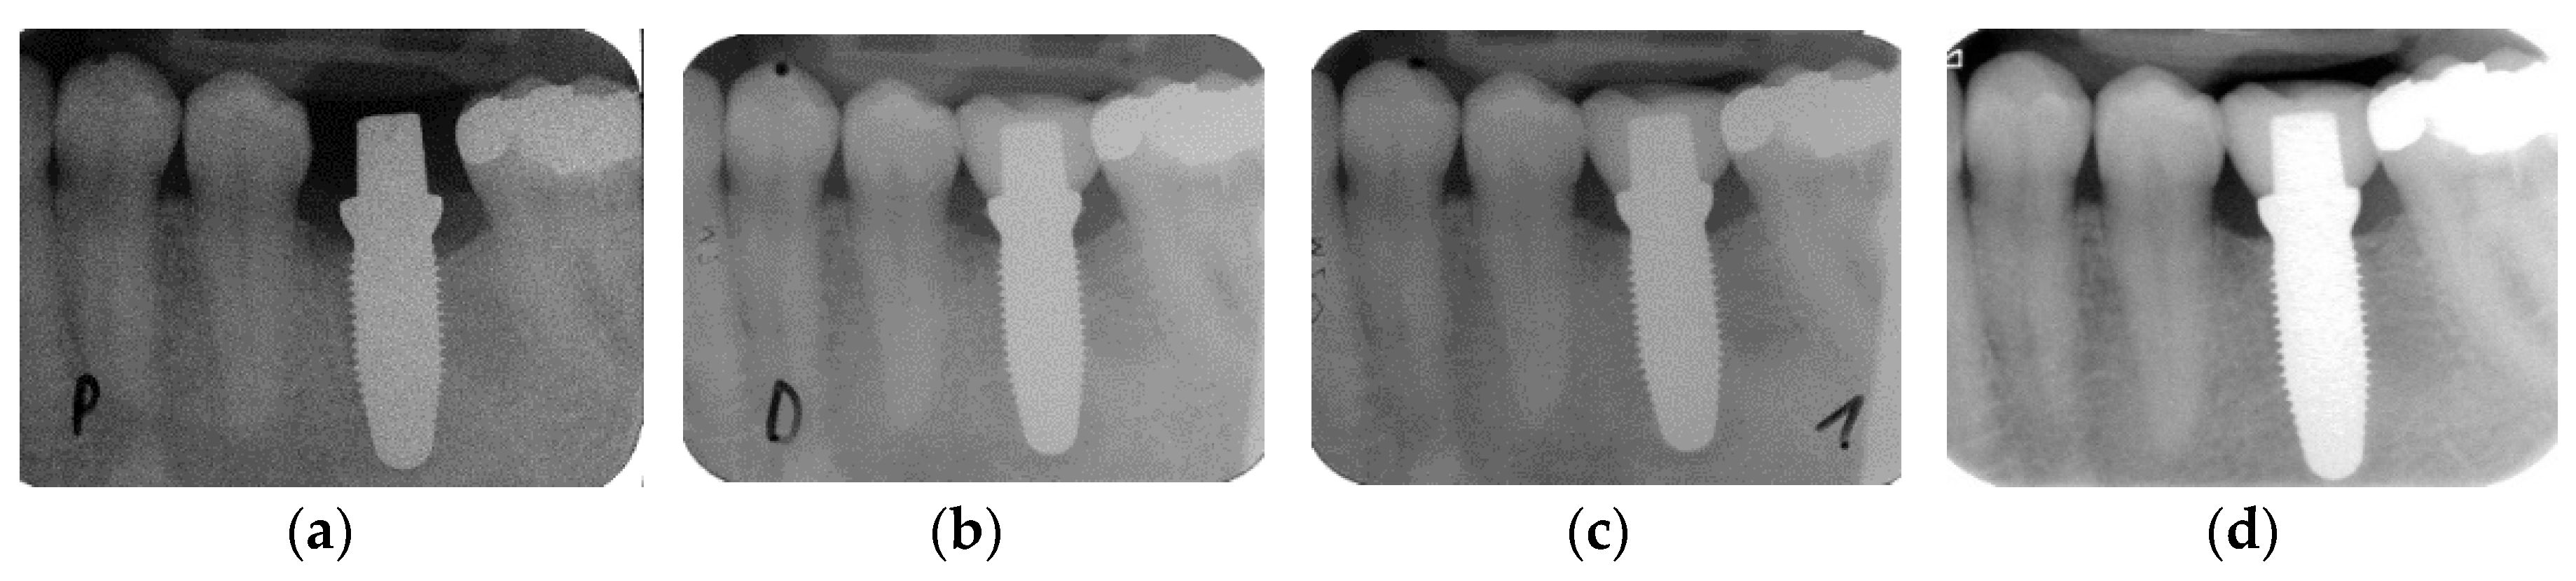

3.2. Marginal Bone Loss